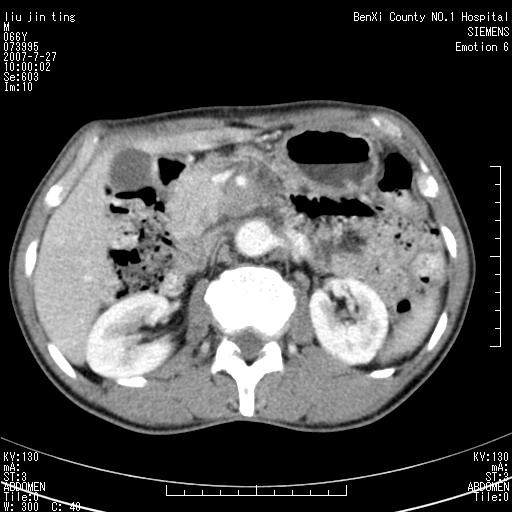

腹痛,背痛,无恶心呕吐,不黄,彩超示胰腺钩癌,ct扫描病灶平扫30-40hu,增强后动脉期40--60hu,静脉期50-68hu,真的是钩突上的么?您要试一试么?

动脉期

静脉期

沿着肠系膜上动脉呈匍匐性生长的软组织肿块,形态不规则,包绕肠系膜上动脉,呈明显强化,考虑来源于肠系膜的恶性肿瘤

肠系膜根部肿块,累及肠系膜上动脉,考虑肿大淋巴结累及肠系膜上动脉.

腹腔干至肠系膜上动脉水平肿大淋巴结影可能性大.